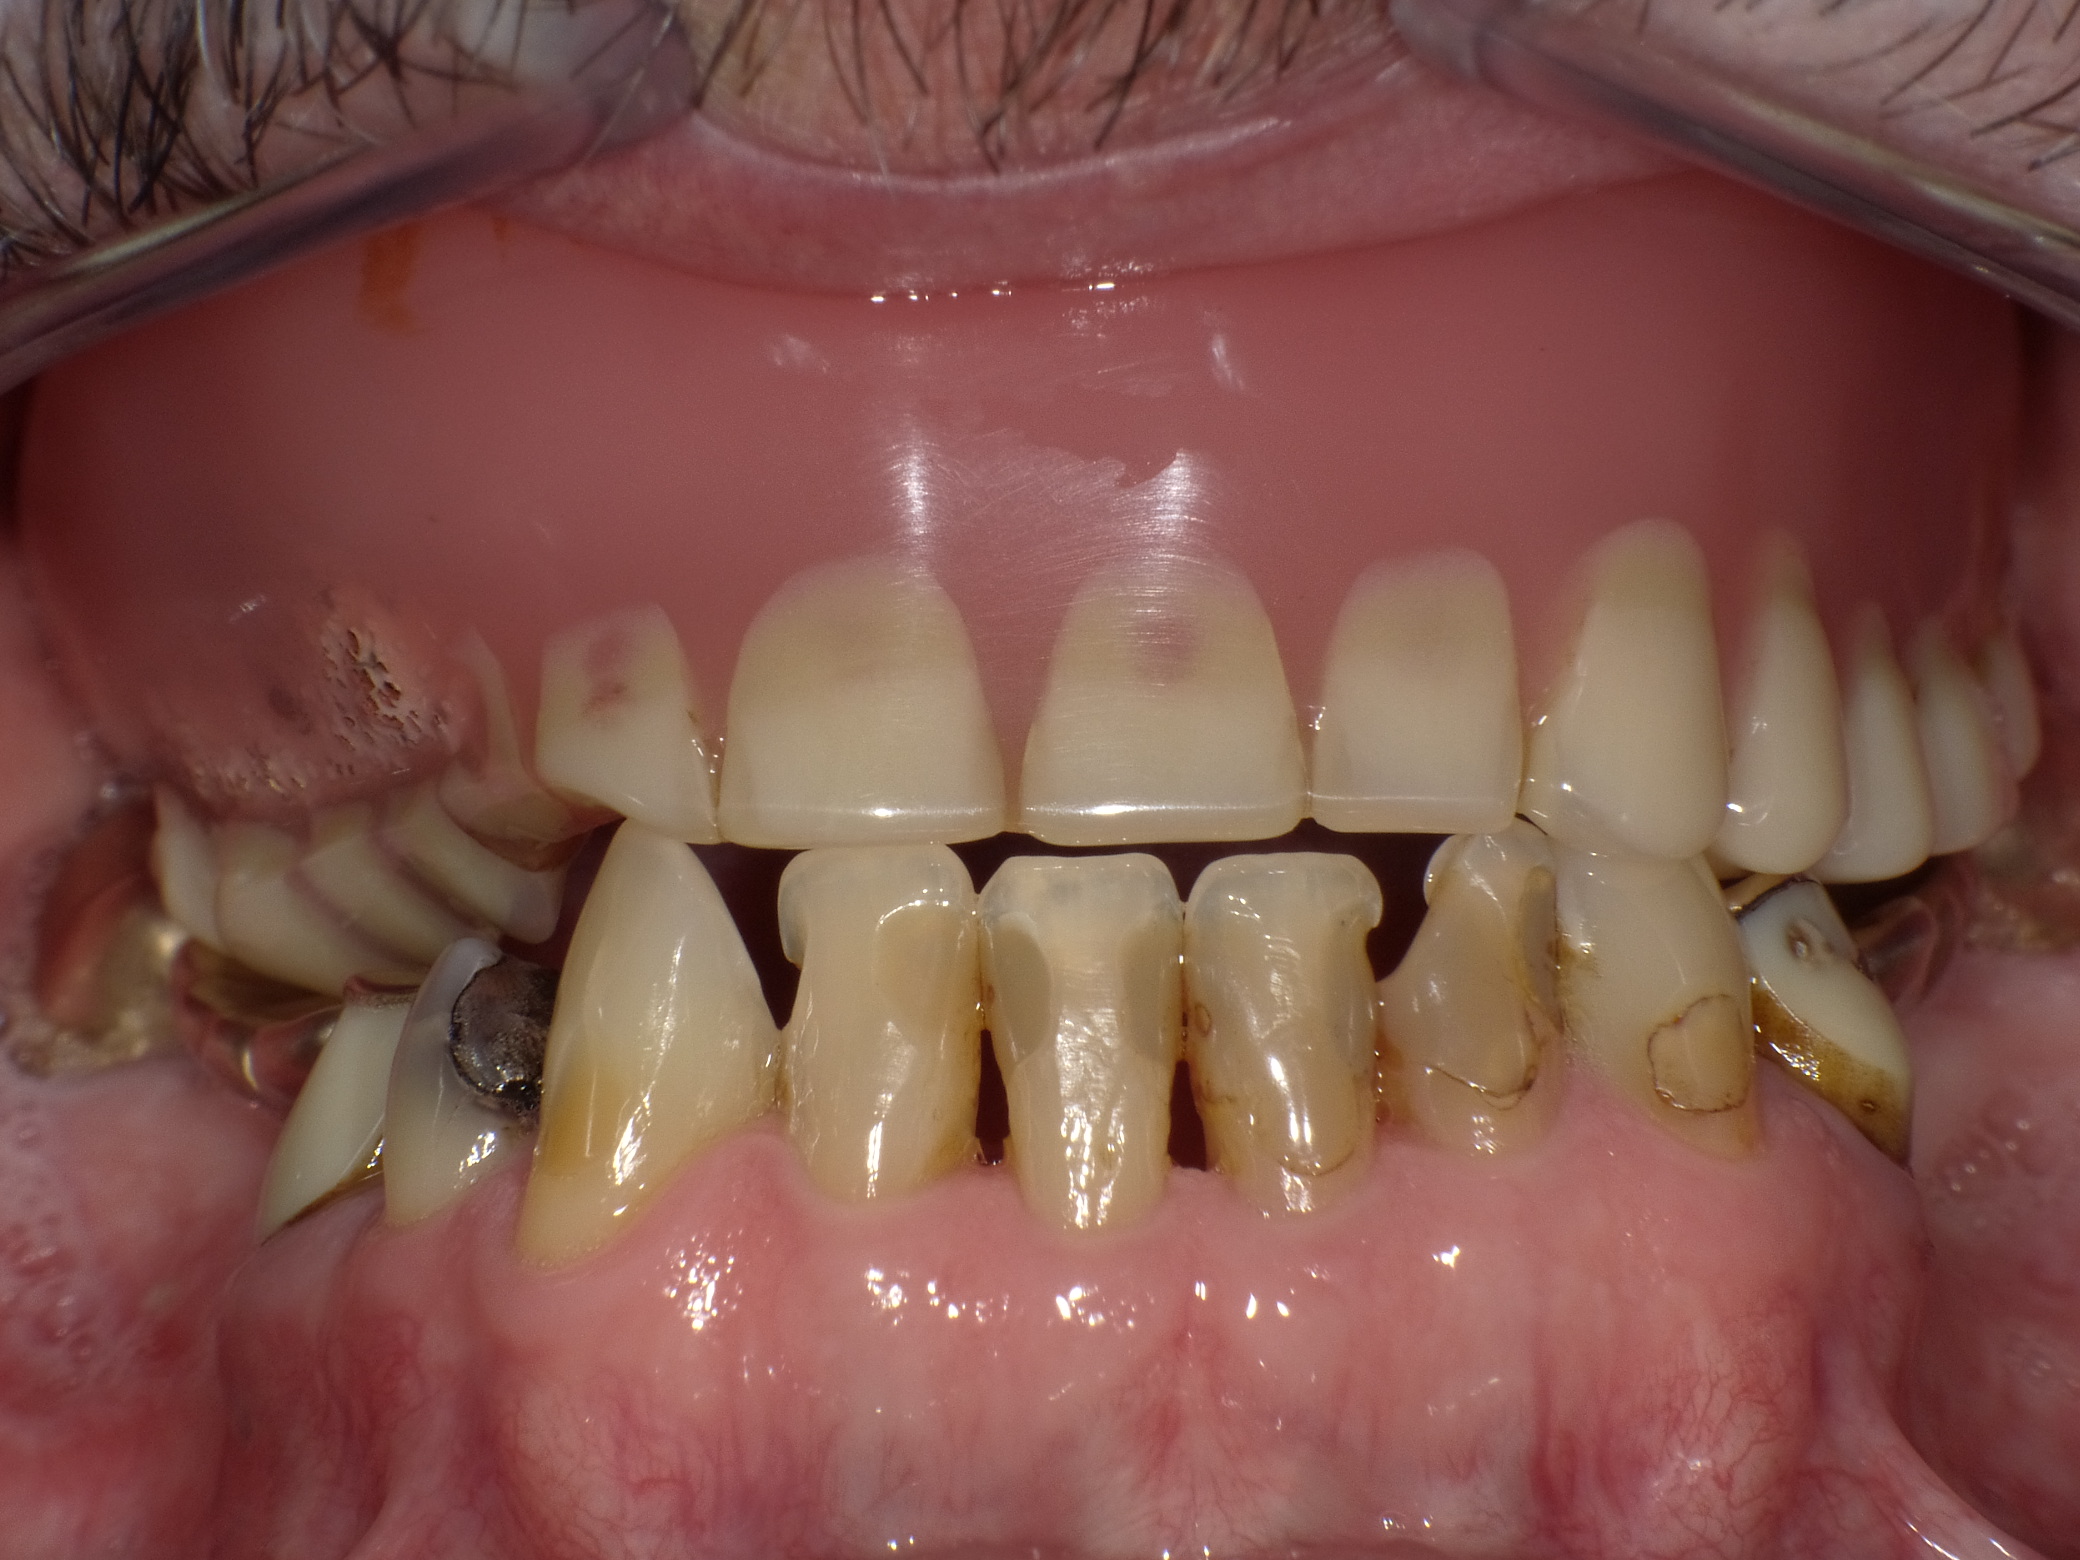

Unbefriedigende Ästhetik, vor allem aber Entzündungen im Knochen und eine massive Parodontitis mit bereits gelockerten Zähnen

Vorher: Unbefriedigende Ästhetik, vor allem aber Entzündungen im Knochen und eine massive Parodontitis mit bereits gelockerten Zähnen

Gesamtbehandlung in Sedierung: die Seitenzähne wurden durch Keramik-Implantate (Zahnentfernungen und Sofortimplantation) mit Knochenaufbau ersetzt; anschließend Gesamtüberkronung aus Vollkeramik mit Optimierung der Ästhetik

Nachher: Gesamtbehandlung in Sedierung: die Seitenzähne wurden durch Keramik-Implantate (Zahnentfernungen und Sofortimplantation) mit Knochenaufbau ersetzt; anschließend Gesamtüberkronung aus Vollkeramik mit Optimierung der Ästhetik